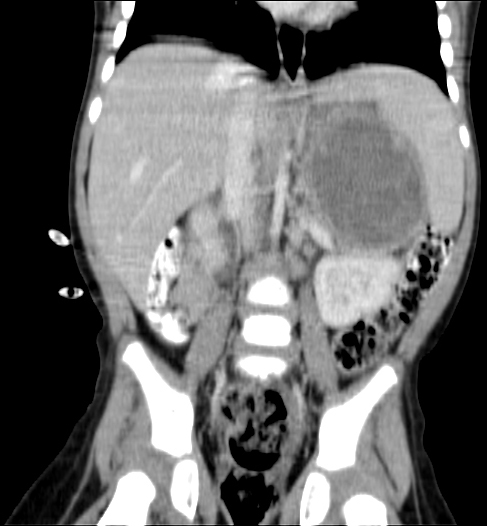

Today we got the Radiology Report back of the 25 August CT (CAT) scan. Papa still has a few remaining questions about it but it confirmed that the tumour shrank as papa thought to see himself from the images. Good news!

Papa collected copy of CT (CAT) scan images from Radiology. Looking at them it seems that the main tumour shrank from around 11 cm to 6 cm and there is less evidence of Nodes. But we have to await Radiology Report to be sure about this positive news. Lets hope Papa is right.

CT (CAT scan) abdomen under anaesthetic, confirms cancer. We await the Radiology Report. There is no way knowing what kind of cancer, but it is suspected maybe Neuroblastoma. We learn that there are different types of Neuroblastoma some of which are low risk and can easily be treated or removed. It is very worrying not knowing more.